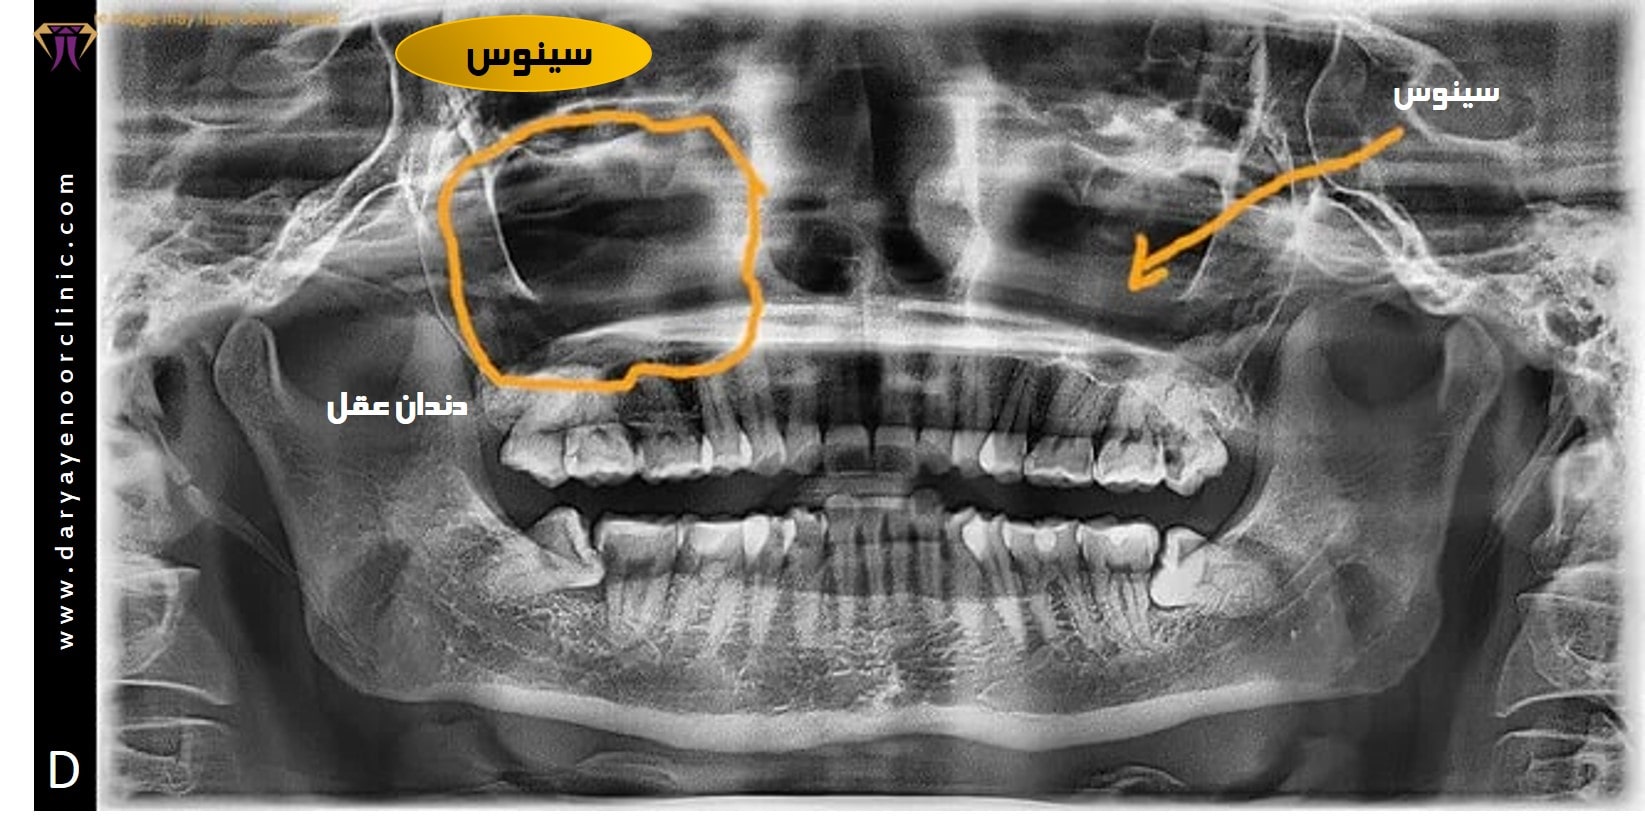

به صورت کلی دندان عقل در قسمت عقبی هر چهارچوب دندانی (کوادرانت) قرار میگیرد. نزدیکی دندان عقل به سینوس که در فک بالا رخ میدهد، هنگامی رخ میدهد که ریشه های دندان عقل فک بالا نزدیک به سینوس فک بالا قرار دارند یا در برخی موارد ممکن است به داخل سینوس فک بالا نفوذ کنند. برای درک بهتر این عارضه که موجب نگرانی برخی از مراجعین میگردد؛ چند نکته کلیدی برای درک بهتروجود دارد.

سینوس ماگزیلاری یک حفره پر از هوا است که در فک بالا قرار دارد، در واقع سینوس ها یک فضای هوایی توخالی در داخل استخوان های جمجمه، صورت و پشت گونه قرار دارند. آنها با یک غشای مخاطی در ارتباط با حفره بینی هستند. و نقش مهمی در مرطوب کردن و فیلتر کردن هوایی که تنفس می کنیم و همچنین تولید مخاط برای مرطوب نگه داشتن مجاری بینی ایفا می کنند. سینوسهای فک بالا که در بالای دندانهای بالایی قرار دارند ممکن است باعث عارضه و درد شوند، و به ویژه در مورد دندان های عقل نزدیک به سینوس ها.

آیا ریشه دندان عقل در سینوس قرار دارد؟

نزدیکی دندان عقل به سینوس می تواند در بین افراد متفاوت باشد. در اغلب موارد، ریشه های دندان عقل فک بالا، دور از سینوس قرار دارد و مجاورت قابل توجهی با سینوس نخواهد داشت. این وضعیت ایده آل در نظر گرفته می شود. در مقابل ریشه دندان عقل ممکن است بسیار نزدیک به سینوس اما بدون تماس مستقیم، باشد؛ در این شرایط جراحی دندان عقل ممکن است، لزوماً مشکلاتی ایجاد نکند، اما برای تشخیص زودهنگام و درمان معایینه مستمرامری ضروری است.

از موارد بعدی که ما شاهد آن هستیم، هنگامی است که ریشه های دندان عقل، بدون نفوذ به داخل فضای سینوس، تنها در تماس با سینوس هستند . اصطلاحا در نزدیکی کف سینوس فک بالا بلند شوند یا به آن فشار وارد کنند. این وضعیت نیاز به نظارت دقیق توسط متخصص جراحی فک و صورت دارد، و در صورت دردهای مزمن دندان عقل و دردهای سینوزیت نیاز به جراحی دندان عقل نزدیک به سینوس وجود دارد. در موارد شدیدتر، ریشه های دندان عقل ممکن است در واقع به سینوس ماگزیلاری نفوذ کند. این وضعیت به عنوان "ارتباط سینوسی" شناخته می شود و خطر بیشتری از عوارض، از جمله احتمال عفونت سینوسی را به همراه دارد.